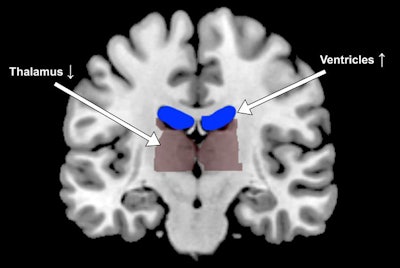

When the participants exercised, sweated, and drank water, fMRI showed that ventricles in the brain contracted. However, with exertion and dehydration, the ventricles did the opposite and expanded, making the thalamus more compact.

"The structural changes were remarkably consistent across individuals," said principal investigator Mindy Millard-Stafford, PhD, a professor in Georgia Tech's School of Biological Sciences, in a statement from the college. "But performance differences in the tasks could not be explained by changes in the size of those brain areas."